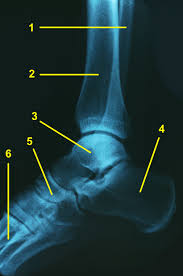

Fußknochen an der seite. Nachdem der erste Anlauf ein Eltern- Lehrerinnen- Team auf die Beine zu stellen im vergangenen Jahr an körperlichen Gebrechen gebrochener Fußknochen gescheitert war starteten wir in diesem Jahr einen neuen Versuch lauffreudige Menschen für den Hanauer Stadtlauf zu begeistern. Der Fuß besteht aus Fußwurzelknochen Mittelfuß und den fünf Zehen auch Vorfuß genannt. Der Fuss ist an der Stelle mit dem Körper verbunden wo Knochen des Rückfusses auf das Schien- und Wadenbein treffen Knöchel.

Andere Erkrankungen der Füße entstehen durch Krankheiten die viele Bereiche des Körpers betreffen wie Diabetes mellitus Gicht oder andere Arthritisformen. Die Knochen des Fußskeletts werden durch zahlreiche Bänder zusammengehalten und sind durch Gelenke miteinander verbunden. Alle von diesen Cookies erfassten Informationen werden aggregiert und sind deshalb anonym.

Den gesamten Komplex bilden außerdem Gelenke Fußwurzelgelenke Gelenke der Mittelfußknochen und Zehengelenke viele für die. Eine weitere Ursache für Schmerzen an der Fußaußenseite ist die Fraktur des fünften Mittelfußknochens. Der menschliche Fuß besteht aus 26 Knochen.